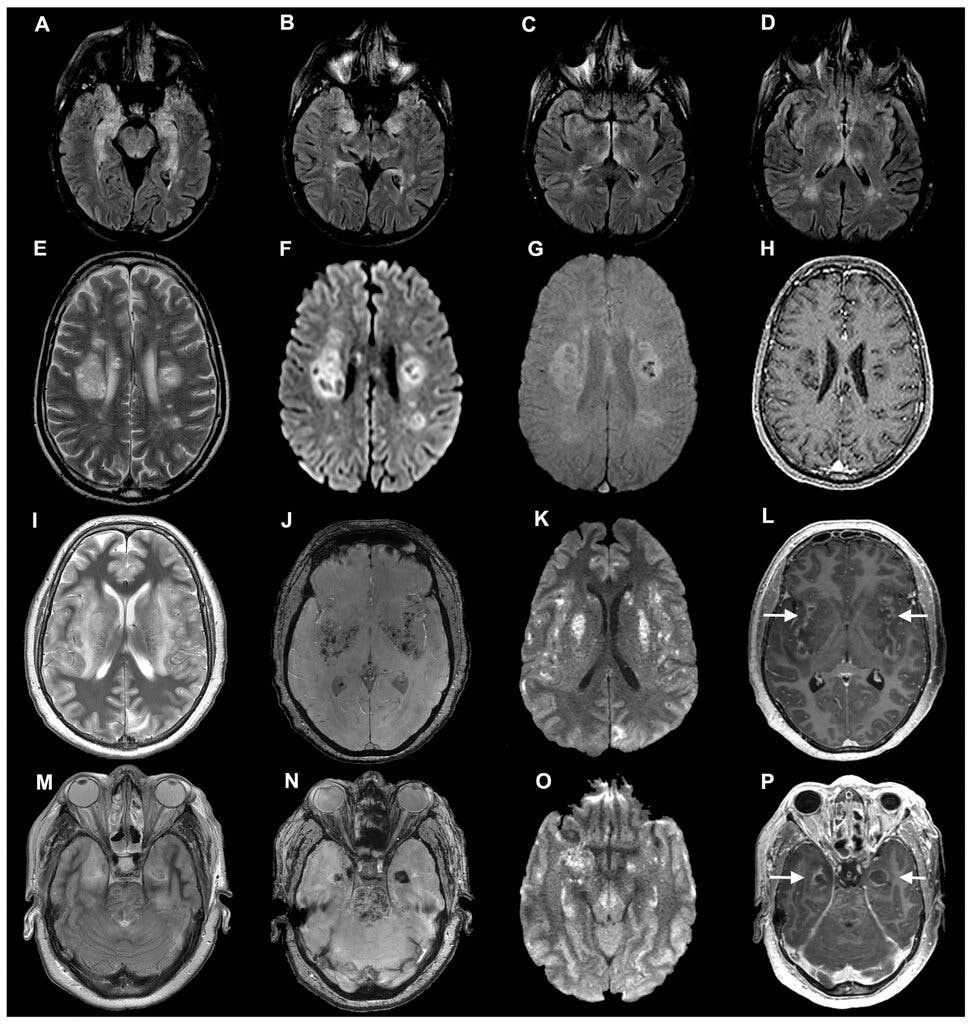

Hình ảnh scan não của các bệnh nhân Covid-19 trong một nghiên cứu của các nhà khoa học Đại học Oxford. Ảnh: New York Times.